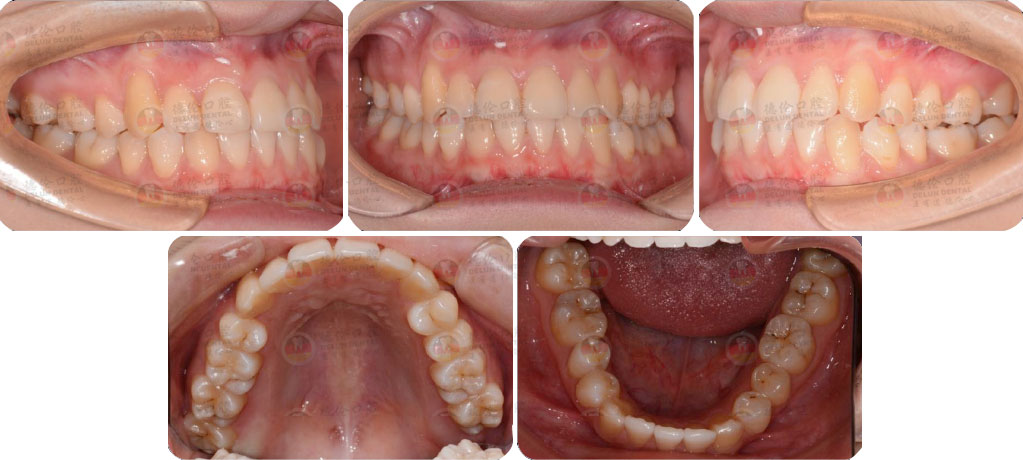

- 【診斷】

骨性Ⅱ類高角伴擁擠

上頜前突、下頜后縮、下前牙唇傾

下中線右偏2.5mm,21 35°扭轉(zhuǎn)13低位

打造醫(yī)生:德倫口腔正畸中心熊小琴主任

- 【治療方案】

拔除3顆多余的咬合不正的智齒,通過(guò)支抗釘控制

失狀向和垂直向,推上、下牙遠(yuǎn)移解決擁擠改善前

突,使整個(gè)頜平面逆時(shí)針旋轉(zhuǎn),改善了下頜后縮的

情況

矯治前后對(duì)比

牙列整平排齊,前牙內(nèi)收;覆蓋、覆合正常;尖牙和磨牙達(dá)到中性關(guān)系;上下中線對(duì)齊;下頜后縮改善